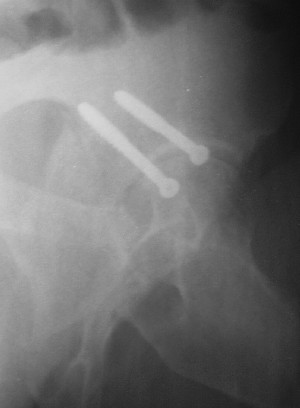

Привет! Вот недавно прооперировали похожий на ваш случай - впадина + шейка (правда у нас впадина поперечный+задний край). После травмы прошло 4 недели. мужчине 46 лет. С такой комбинацией все показания к первичному протезированию. Морально и технически мы к этому уже созрели.Но больной не собрал денег на протез. Выполнили остеосинтез впадины и шейки, прекрасно понимая, что головка вскоре рассосется, мы хотя бы надемся что к этому времени таз срастется, как говорится создали все условия для дальнейшего протезирования (может, и протез в последующем подешевле будет, в смысле, без укрепляющего кольца?). Привет Рункову!

Привет Алекей! Сделано неплохо, поздравляю, хотя второй винтик можно было бы и подлиннее в шейку загнать! Пара вопроов: доступ такой же? головка была свободной или висела на капсуле?

Согласен, можно было и подлиннее. Доступ такой же - чрезвертельный, только разрез кожи прямой (а не Y, чего то я разницы не ощущаю). Головка была абсолютно свободной (то есть во время остеосинтеза таза лежала в стакане и не мешалась). Шансов, что она прирастет 0,00001%. Хотели даже выбросить, но привинтили как временный биологический протез (читай свободный трансплантат), чтоб на период срастания таза бедро проксимально не ушло (может ортопеды потом спасибо скажут). Ну а у вас первичное протезирование при переломе впадины тоже пока полько в планах?